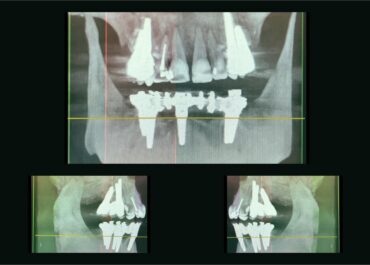

Durante una scansione cone beam, la macchina ruota intorno alla testa del paziente, acquisendo centinaia di immagini da diverse angolazioni. Queste immagini vengono poi elaborate per generare una rappresentazione tridimensionale delle strutture interne, comprese le ossa, i denti e i tessuti molli.

Il raggio conico proiettato dal dispositivo consente di catturare una grande quantità di dati in un solo ciclo di scansione, riducendo i tempi e l’esposizione ai raggi X rispetto alla TC convenzionale. Il risultato è un’immagine dettagliata che può essere visualizzata da diverse prospettive e piani, facilitando una diagnosi precisa.